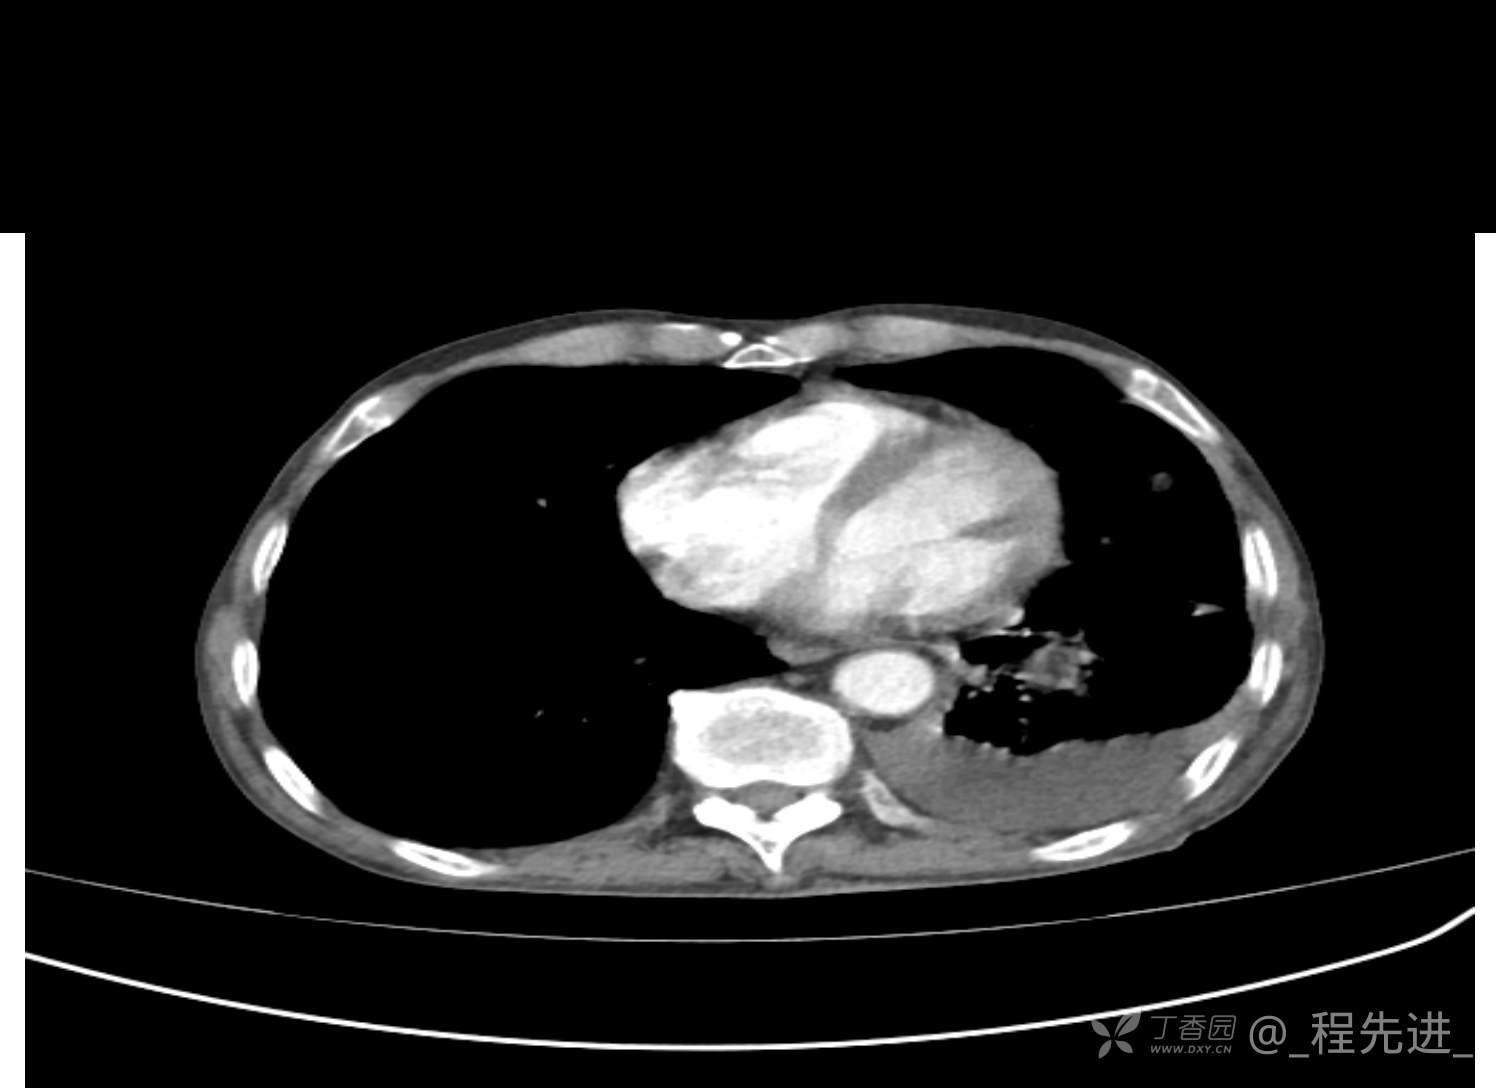

患者性别:男

患者年龄:81岁

简要病史:反复咳嗽、咳痰20余年,加重1周。两肺呼吸音低,可闻及散在干湿啰音。